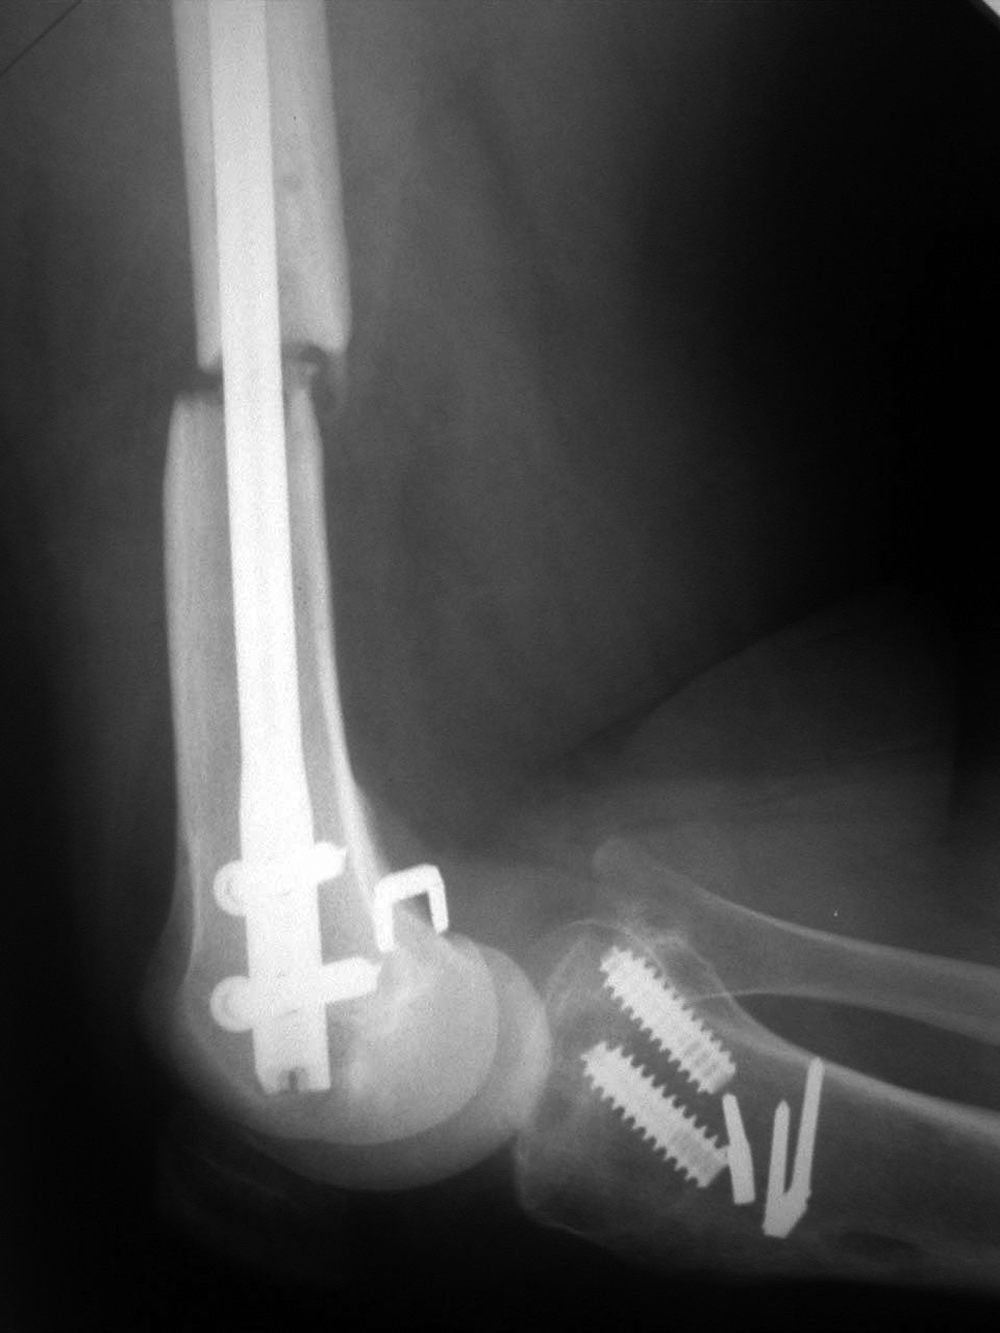

AP and lateral views of the knee show a distal femoral cadevaric limb sparing allograft approximated to the native distal femoral stump by a retrograde intramedullary nail. Two interlocking cannulated screws go through the distal portion of the nail. Cruciate ligament and capsular reattachment were performed with two interference screws and two staples in the proximal tibia and a staple in the posterior aspect of the allograft metaphysis. The patient had a non-specified distal femur sarcoma.